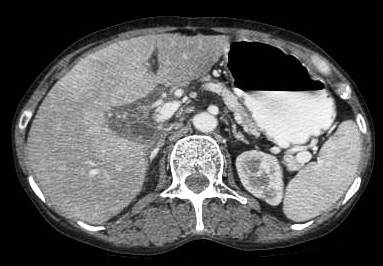

Common patterns of carcinoma gallbladder

Three patterns have been described on ultrasonography (US). The gallbladder fossa is replaced by a heterogeneous mass (figure 1) with internal areas of necrosis; or there may be diffuse, irregular, and asymmetrical wall thickening (Figure 2); or less commonly, a polypoidal, fungating intra-luminal mass is seen. Correct preoperative diagnosis has improved considerably with the use of newer imaging techniques [6-8]. Majority of cases when diagnosed, are no longer resectable (Figure 3) [9-11].

Figure 1: large gallbladder fossa mass replacing the entire gall bladder. Discrete liver secondaries can be seen.

Figure 1: Large gallbladder fossa mass replacing the entire gallbladder. Discrete liver secondaries can be seen.